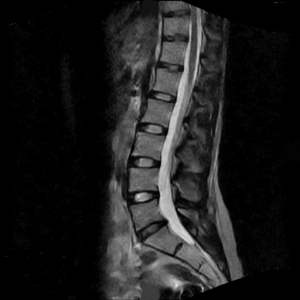

MRI

An MRI is a non-invasive study that provides a clear diagnostic picture without using radiation. It can clearly show soft tissue structures that are not seen on routine x-rays, such as herniated discs, nerves, muscle, infections, and tumors.